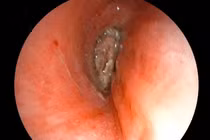

Các bác sĩ Bệnh viện Nhi đồng 2, TP HCM vừa phẫu thuật thành công, lấy ra dị vật là cành cây dài 16cm, đường kính 1cm nằm trong ổ bụng bé gái 3 tuổi suốt hơn 4 tháng.

Tại đây, kết quả CT scan cho thấy trong ổ bụng bệnh nhân có dị vật kích thước 1x16cm nằm từ trực tràng đến gan.

Ê-kíp nội soi xác định, dị vật đâm xuyên trực tràng, ruột non và tá tràng ruột viêm dính nhiều, gây khó khăn cho phẫu thuật vì ruột dính nhiều. Các bác sĩ tiến hành mổ mở bóc tách dọc theo dị vật, tách dính toàn bộ ruột, tránh làm tổn thương các mạch máu thần kinh và niệu quản, hạn chế các tổn thương các bộ phận khác.

Sau 4 giờ phẫu thuật, các bác sĩ đã lấy ra nguyên vẹn cành cây dài 16cm. Bệnh nhân được xử lý cầm máu, khâu các vết thương và làm hậu môn tạm. Hiện sức khỏe bệnh nhi đang dần hồi phục, dự kiến sẽ xuất viện sau 1 tuần.